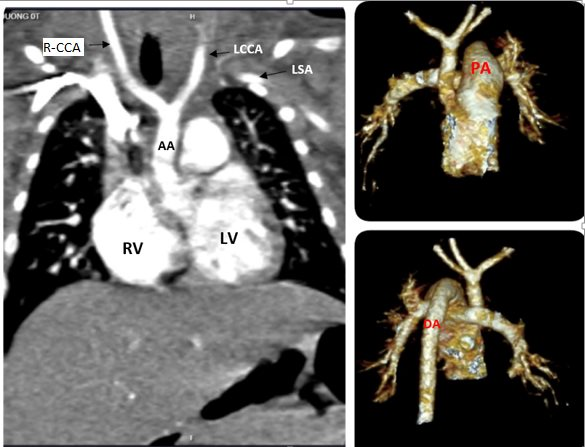

Gián đoạn quai động mạch chủ ở trẻ trên phim chụp.

Kết quả cắt lớp vi tính động mạch chủ ngực: Gián đoạn quai động mạch chủ đoạn sau động mạch dưới đòn trái (type A). Động mạch chủ xuống liên tục với động mạch phổi qua PDA lớn. Thông liên thất.